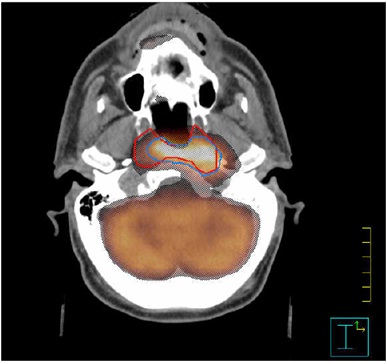

Hình ảnh PET/CT của bệnh nhân ung thư vòm, loại không biệt hóa: đường đỏ xác định bằng CT, đường xanh xác định bằng PET

Kết quả về xác định thể tích khối u thô cho thấy thể tích trung bình của PET/CT-GTV là 26,0 cm3 có thay đổi so với CT-GTV là 20 cm3 và PET-GTV là 17,2cm3 (p<0,001) cho thấy xác định thể tích u thô trên PET kết hợp cả CT có độ chính xác hơn.